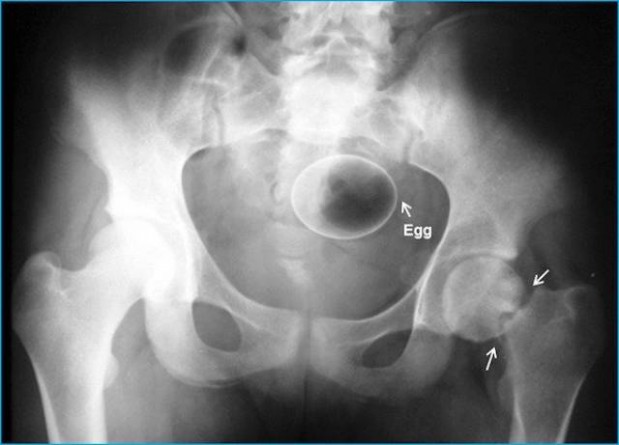

#7 Kananmuna